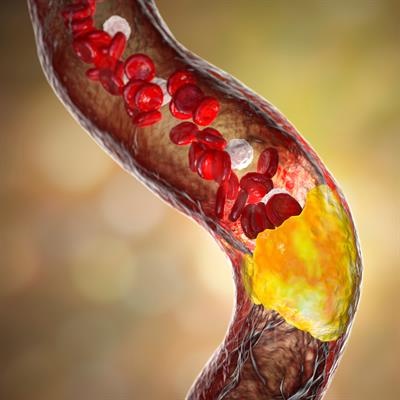

Challenges in the Contemporary Assessment of Coronary Physiology

- Dejan Orlic

- Milorad Tesic

- 16,269 views

- 6 articles